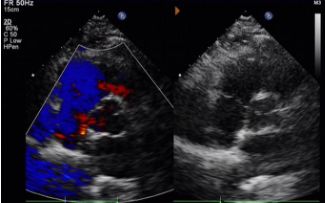

Key Follow-Up Imaging Findings

Day 1 to 9 Months:

No residual shunt observed.

Gradual reduction in device echogenicity.